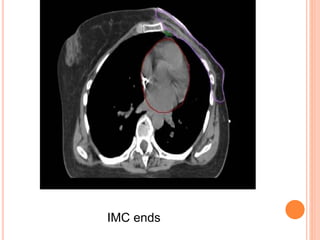

REGIONAL NODAL CONTOURING

SCF begins

Axillary level III begins

Axillary level II begins

Axillary level I begins

Axillary level I ends

IMC begins

IMC ends